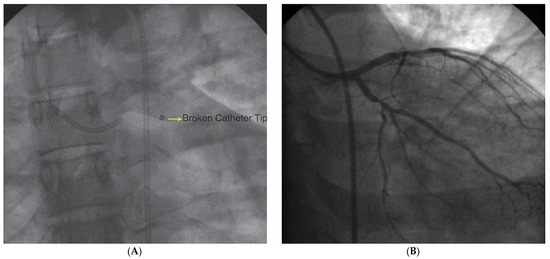

Case report